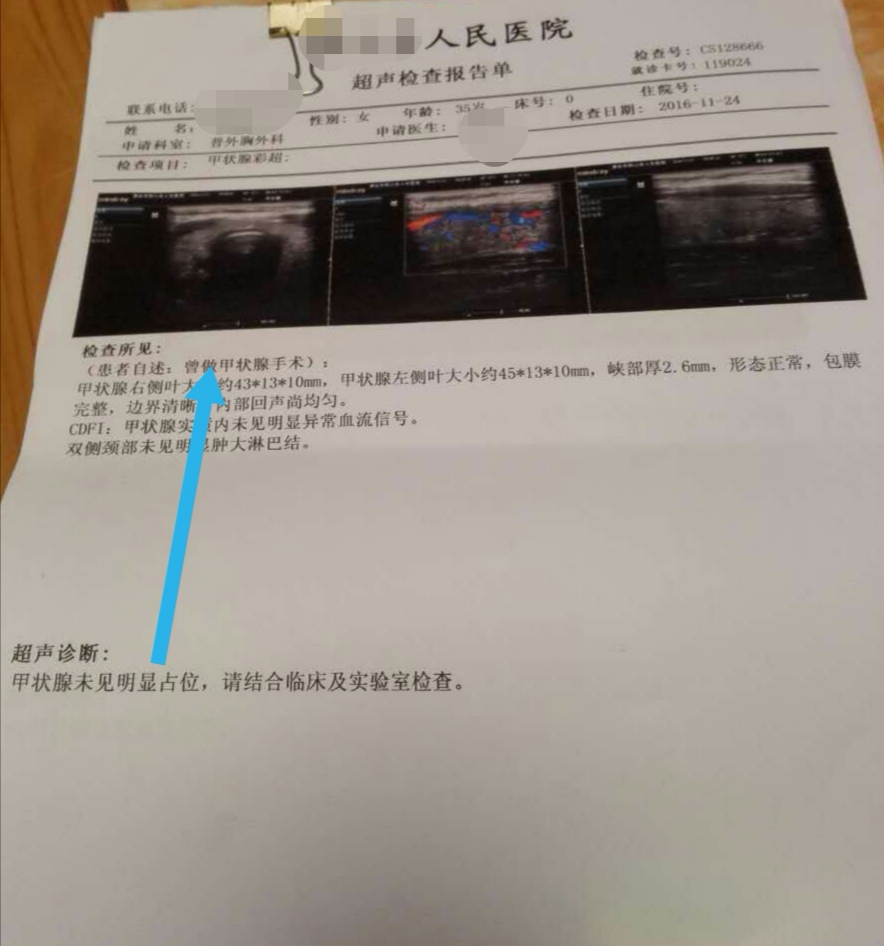

李女士微创介入消融治疗后1年(2016年11月)在当地医院复查超声显示甲状腺多发结节消融后均吸收消失(如下图)。